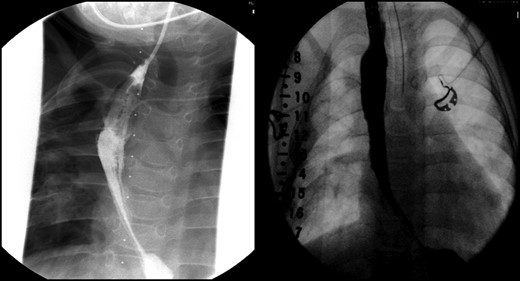

Daily tightening of her traction sutures was performed until the distal esophageal segment reached the chest wall (Fig. 2). The cervical esophagostomy was also sequentially lengthened and eventually internalized. Three traction suture revisions and two proximal esophageal lengthening operations were performed before esophageal continuity was re-established (46 days). Two subsequent anastomotic leaks occurred; 1 anastomotic leak was repaired surgically, whereas one subsequent leak was managed nonoperatively with a chest tube. Five dilations and, one, 13-day retrievable stent placement were needed for anastomotic narrowing. A comparative postoperative esophagram and intraoperative esophagram illustrated neither a stricture nor an anastomotic leak (Fig. 3). Total hospitalization was 112 days.

An intraoperative esophagram following a routine esophagogastroduodenoscopy (EGD) is pictured on the right, as compared with her postoperative esophagram on the left. The EGD was performed on this patient following her anastomosis (Foker Stage II); the native esophagus was now in continuity. Contrast was injected above the level of the anastomosis, which demonstrated neither leak nor stricture.